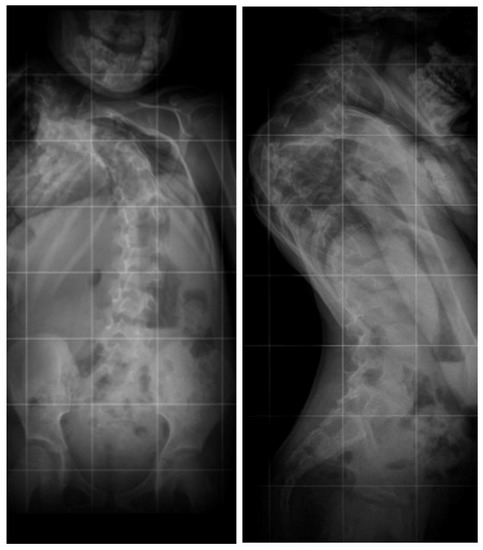

Angio-CT examination of blood vessels in the neck, chest, and abdomen showed no pathological structure. The patient underwent posterior vertebral column resection of T3–T4 (the blocked vertebrae) using the costotransversectomy approach (Figure 4 and Figure 5) with posterior pedicle screw stabilization and fusion between C7 and T9.

Correction of the deformity included right-sided compression and left-sided distraction. The pleura remained intact during the surgery, and no chest tube was needed (Figure 6).

Figure 4. Posterior approach to the cervical and thoracic spine.

Figure 5. Posterior instrumentation and correction of C7–T9.